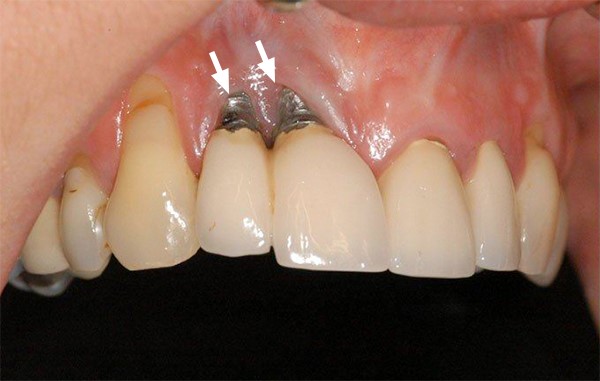

Viêm quanh trụ là tình trạng nhiễm trùng làm tổn thương mô nướu và xương quanh trụ Implant. Nguyên nhân thường do đặt trụ sai vị trí, trụ Implant chất lượng kém hoặc bệnh nhân không được hướng dẫn chăm sóc đúng cách. Nếu không điều trị kịp thời, tình trạng viêm sẽ trở nên nghiêm trọng hơn hoặc đào thải trụ ra bên ngoài.

Bác sĩ cắm trụ sai vị trí, đặt trụ implant quá sâu vào xương hàm có thể gây va chạm các xoang hoặc dây thần kinh bên dưới. Khi đó bạn có thể gặp các triệu chứng như ê buốt, tê hoặc đau nhức kéo dài.